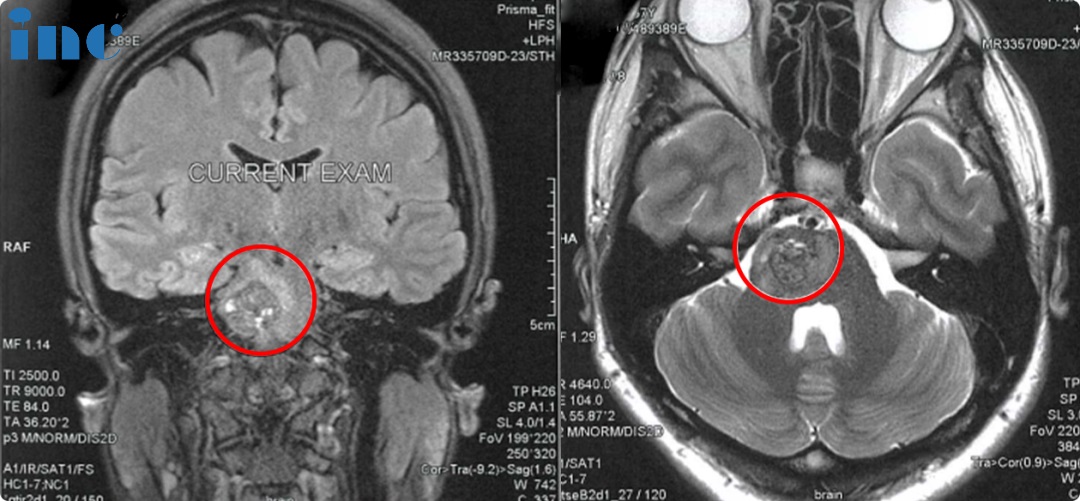

顺利全切脑干海绵状血管瘤手术回顾

2023年巴教授9月中国行期间,一场疑难脑瘤示范手术成功拯救了年轻的佩珊于病魔的阴影之中。经INC巴教授成功手术后,不仅得到了全切,且较害怕的偏瘫、面瘫等也没有发生,也不需要后续放疗辅助,在ICU待了一天就出来了。这个结果对37岁的脑干海绵状血管瘤患者佩珊来说也是幸运之神降临。术后3天,巴教授查房时,佩珊看到前来问候查房的巴教授时,手舞足蹈、开心比心。兴奋的她激动得对巴教授“表白”感谢:“巴教授您太帅了,I Love you!巴教授也跟佩珊开心得比心。她的治疗路上充满挣扎和痛苦,但更多的却是驱散黑暗的明媚阳光。

人们常说病来如山倒,脑干海绵状血管瘤就是这样一种良性,但是却能消磨人的意志,夺去你生活的希望,将你拉进痛苦深渊的疾病。脑干,无论手术还是不手术,都存在致残风险,应该如何选择治疗方案呢?还能回归健康生活吗?

佩珊术前是什么情况?有出过血吗?

佩珊:出过一次,大概7月31号。出血后就没力气了,在香港当地医院做核磁,发现脑干那里出血了。出血后左边身没力,左边脚没力。后面就慢慢恢复了。我是出过一次血,恢复了全部正常,就不想出二次血,就很怕出二次血。

巴教授术前是如何为佩珊评估的呢?

巴教授远程邮件评估:“我可以为患者完全顺利切除病灶。风险是已经由出血引起的感觉运动缺陷的暂时性的,轻微的听力缺陷和轻微的面部无力,然而,这些副作用无论如何都只是暂时的。手术后出现这种症状的风险可能是5-6%,如果确定是术后出现的,那这种缺陷在手术后1-3个月内得到解决”